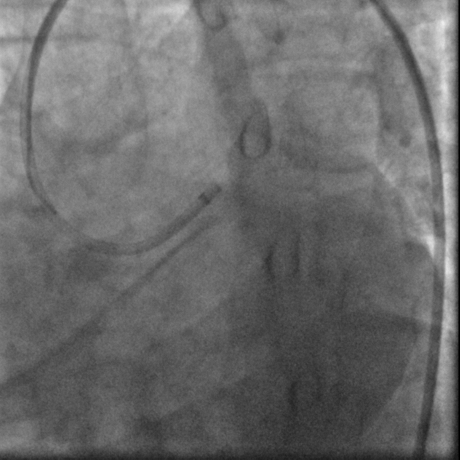

经右股动脉(8F),送EBU 3. 5指引导管指引导管至左冠开口。Sionblue导丝至LCX保护,Finecross 130到达LCX远端待命。Sionblue引导Corsair 135cm微导管进入LAD。近段纤维帽坚硬(伴钙化随后IVUS证实)尝试使用Gaia1st进入前次假腔,导丝升级Gaia 3rd谨慎前进入间隔支S1,推送corsair进入S1交换KDLC,Pilot 200导丝平行进入LAD真腔。Corsair交换Sionblue到LAD远端。IVUS证实全程真腔,闭塞段以纤维为主。植入支架完成血运重建。

G3前进

Pilot扭身进入lad